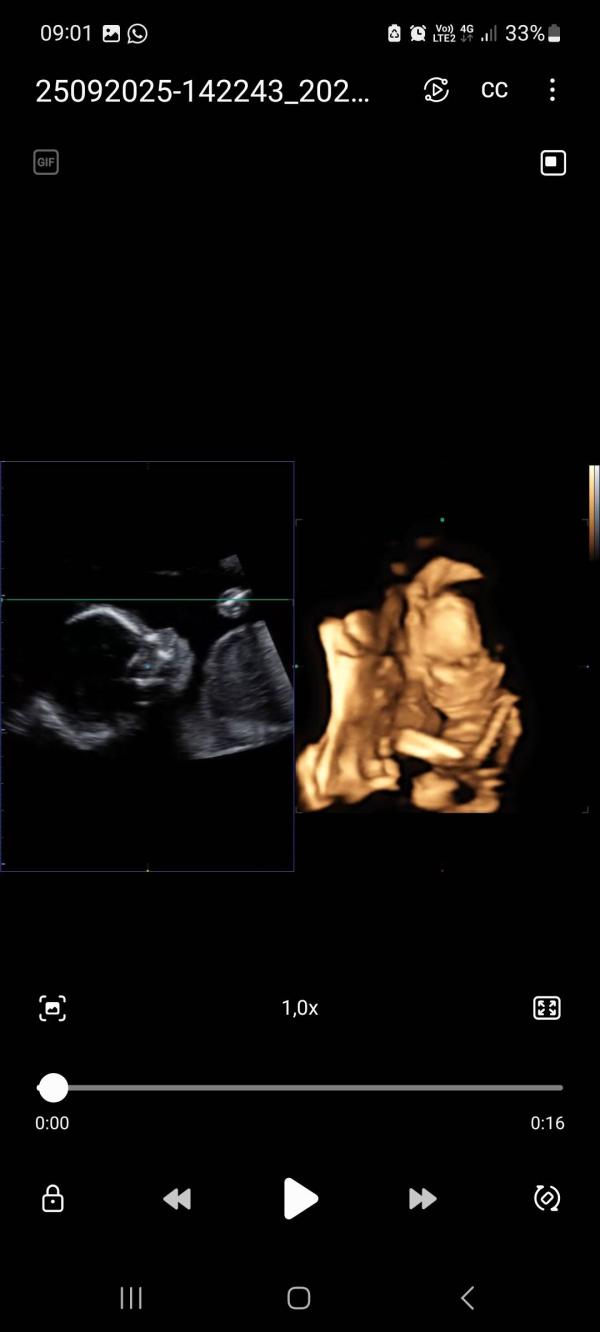

Второй скрининг был успешно пройден ещё 25 сентября 🙏

У меня и у малышки всё замечательно.

Сегодня же уже ровно 22 недели и что имеем на данный момент :